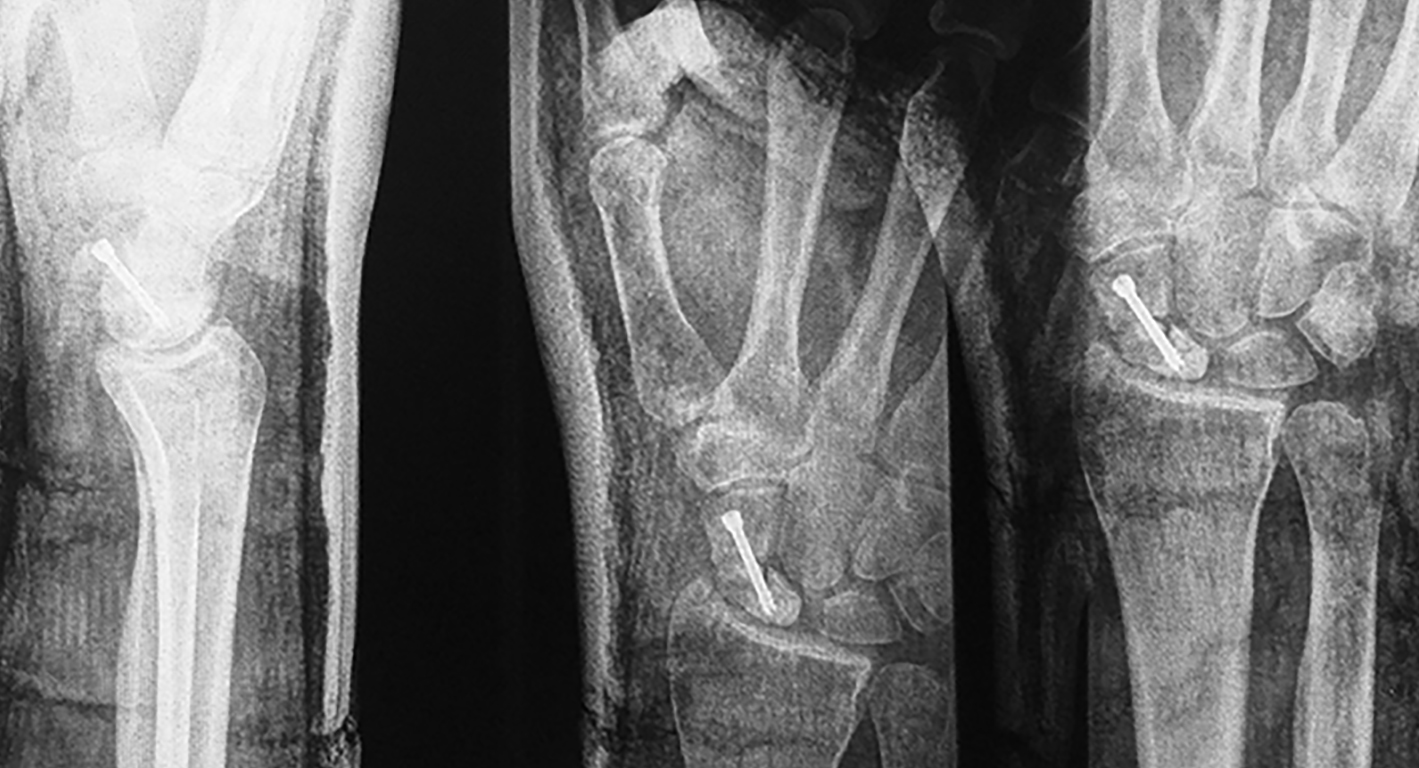

Efectuamos un abordaje volar dado que conserva la vascularización dorsal, permitía la visualización directa del foco, movilización de los polos y manejar la deformidad en joroba mediante el injerto trapezoidal (1)(11)(12). Nos centramos sobre el tendón palmar mayor, efectuando una incisión curvilínea dirigida hacia el tubérculo del escafoides. Se protegió la rama sensitiva cutánea del nervio radial y disecamos el plano superficial incidiendo la cápsula longitudinalmente sobre el eje del escafoides. Se reflejó la cápsula, se identificó el polo distal y proximal colocando dos agujas de Kirschner, a modo de joystick. Cureteamos el foco con una fresa (Figura 1). Dejando el escafoides, extrajimos un injerto cortico-esponjoso trapezoidal de cresta iliaca (Figura 2). Volviendo a la mano, distrajimos los fragmentos escafoideos y colocamos el injerto, con su base en situación volar, para extender el escafoides (1)(5)(12)(13). Colocamos otra aguja de Kirschner retrógrado como guía, y tras medir y mechar, colocamos un tornillo de compresión interfragmentaria (11), para proceder posteriormente a cerrar la cápsula y los planos superficiales. Se colocó una inmovilización con férula de yeso, incluyendo el primer dedo, que mantuvimos durante 4 semanas.

Se efectuaron radiografías dorso-palmar, lateral pre y post operatorias. Al final del seguimiento se evaluó la consolidación mediante radiografías. Se indicó un TC de puño en los pacientes como método de valoración pre operatoria y la RM cuando se sospechó un compromiso vascular del polo proximal para definir técnica quirúrgica.

La evaluación de la movilidad mostró que 5 pacientes (29,4%) tenían la movilidad completa; 11 pacientes (64,7%) la conservaron entre el 75 y el 99 % y un paciente (5,9%) entre el 50 y el 74%. No encontramos asociación estadística entre la movilidad y el retraso terapéutico (p=0,241). (Figura 3) (Figura 4) (Figura 5) (Tabla 1) (Tabla 2).

Figura 4: Caso 12

a) Radiografía de frente pre-operatoria

b) Radiografía pre-opertaoria, enfoque de escafoides

c) Radiografía post operatoria

e) 24 meses de seguimiento. Radiografía de frente

f) 24 meses de seguimiento. Radiografía de perfi